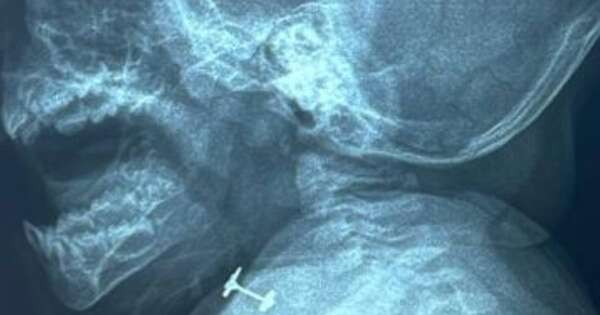

En el Instituto Nacional de Enfermedades Respiratorias y del Ambiente (INERAM) asistieron de urgencia a una beba de 10 meses que llegó con asfixia parcial luego de que un arito se le haya quedado atascado en la laringe. ...[Leer más]